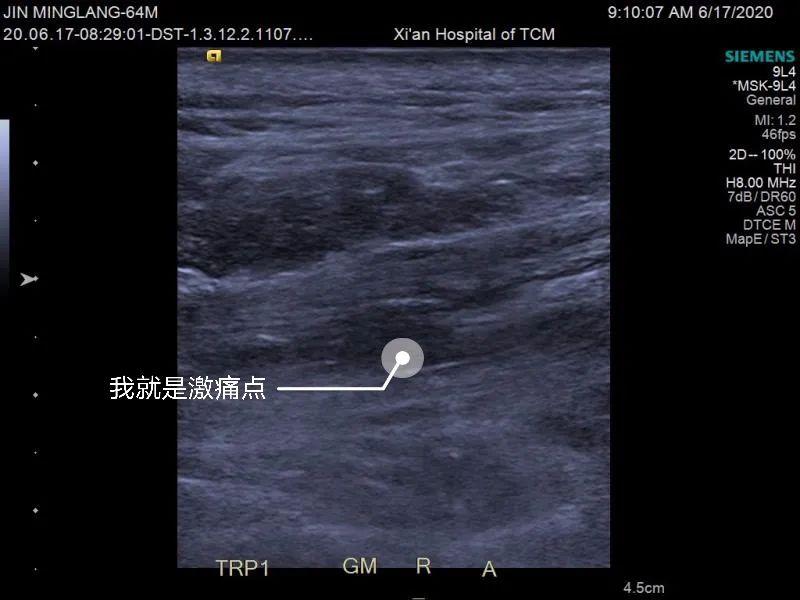

西安市中医医院骨伤科脊柱病区开展新型治疗,将中医传统刃针和“B超”做到有机融合,让痛点暴露在“阳光”下,从而更加精准、快速、高效的治疗。

李女士来到骨伤科脊柱病区门诊,孙晴主任仔细询问了她的工作性质与生活习惯。李女士说日常主要是从事文书工作,一坐就是一天,也没什么运动习惯。结合病史与查体,孙主任判断李女士应属肌筋膜疼痛综合征,建议她做肌骨B超检查,结果显示李女士腰背骨髂肌肉有明显的激痛点。

孙主任告诉李女士,她的腰椎并没有发现器质性病变,疼痛主要和肌肉有关,可以通过刃针治疗来缓解疼痛。李女士担心治疗过程中的疼痛与创伤,孙主任耐心解释:刃针非常细,有创伤小、疗效好的优势,在B超引导下治疗会更加安全,几乎不会出血,10分钟之内即可完成治疗。